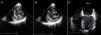

Apresentava no ECG sinais de EAM prévio (fig. 2) e no Rx de tórax observou-se a presença de uma massa adjacente à silhueta cardíaca (fig. 3). Repetiu ecocardiograma, que mostrou um volumoso aneurisma apical que se associava a imagem suspeita de pseudoaneurisma, com extensão ínfero-posterior e compressão do ventrículo direito (fig. 4).

Ecocardiograma transtorácico bidimensional, incidência apical 4 cavidades (painel A), eixo curto (painel B), apical 2 cavidades (painel C) e subcostal (painel D), evidenciando a presença de pseudoaneurisma (Ps) ventricular esquerdo, de colo estreito (seta) e extensão ínfero-posterior, comprimindo o ventrículo direito (VD).